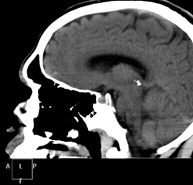

- TC Crani

Prova radiològica que consisteix en obtenir imatges del crani d'alta definició anatòmica (tronc cerebral, cerebel, cervell, calota cranial, etc. ) mitjançant l'ús d'un equip de TC (Tomografia Computeritzada). Indicacions: traumatismes, cefalea, trastorns de la memòria, pèrdua de força sobtada en una extremitat o meitat del cos. - TC Coll